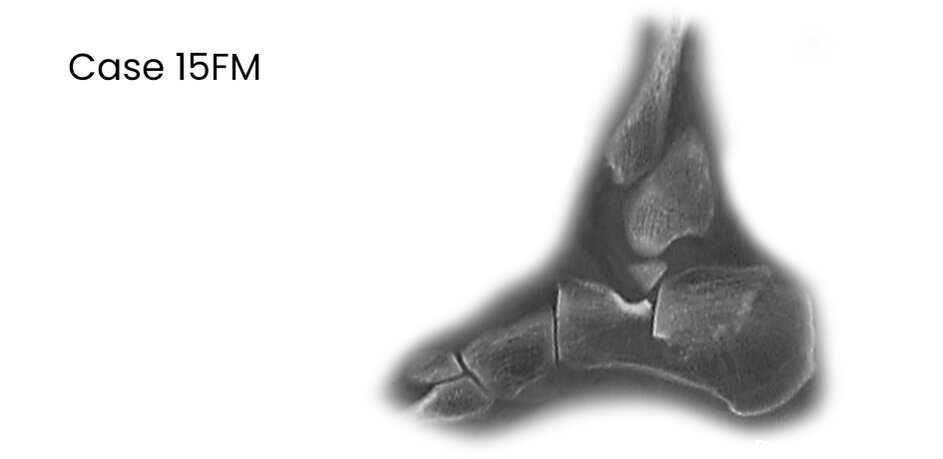

case 15FM, 34y, male, depression-type, surgery on 2nd day after trauma, chain smoker